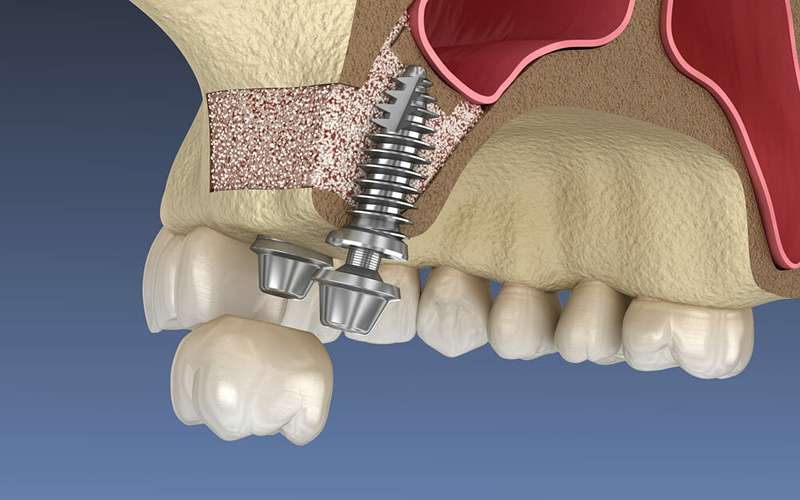

سینوس لیفت یا جراحی بالا بردن سینوس یکی از روشهای تخصصی جراحی دهان و فک است که برای افزایش ارتفاع استخوان فک بالا در ناحیه دندانهای آسیای کوچک و بزرگ انجام میشود.

سینوس لیفت یک جراحی افزایش ارتفاع استخوان در ناحیه عقب فک بالا است که با اضافه کردن استخوان در زیر سینوس انجام میشود تا امکان کاشت ایمپلنت فراهم شود.

وقتی ارتفاع استخوان فک بالا کم باشد (به دلیل تحلیل استخوان یا نزدیکی ریشه دندان به سینوس) و نتوان ایمپلنت را بدون پیوند استخوان قرار داد.

معمولاً بین ۴ تا ۸ ماه زمان نیاز است تا استخوان جدید ساخته و محکم شود، اما در برخی موارد امکان کاشت همزمان ایمپلنت وجود دارد.